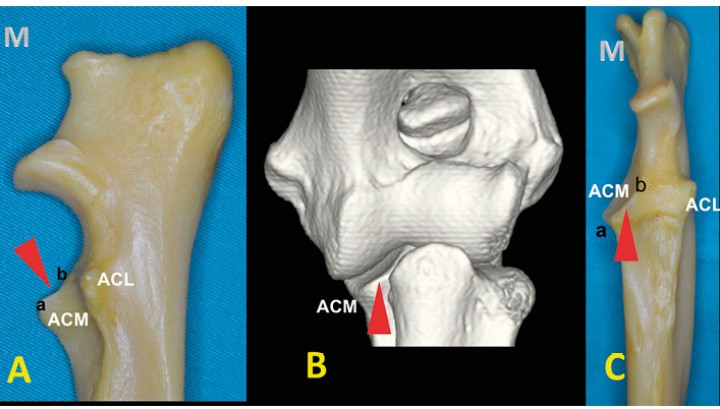

La observación de un cúbito canino permite ver que las apófisis coronoides del perro son completamente distintas. La apófisis coronoides medial (ACM) y la apófisis coronoides lateral (ACL) se disponen a distinta altura situándose la ACL más proximalmente. A su vez, la ACM es inclinada y curva, presentando su base más proximal y lateral que el ápex (Fig. 4) (Vídeo 1).

<p>Cúbito mostrado por las caras medial (<strong>A</strong>) y craneal (<strong>C</strong>) y una imagen tridimensional de un codo sano (<strong>B</strong>). Se aprecia la distinta altura de las apófisis coronoides lateral (ACL) y medial (ACM). Esta última se divide en el ápex (a) y en la base (b). Se puede observar la inclinación de la ACM (punta de flecha roja). Las lesiones de la base no se pueden apreciar en las radiografías craneocaudales, ya que se quedan superpuestas con la epífisis proximal del radio.</p>

Cúbito mostrado por las caras medial (A) y craneal (C) y una imagen tridimensional de un codo sano (B). Se aprecia la distinta altura de las apófisis coronoides lateral (ACL) y medial (ACM). Esta última se divide en el ápex (a) y en la base (b). Se puede observar la inclinación de la ACM (punta de flecha roja). Las lesiones de la base no se pueden apreciar en las radiografías craneocaudales, ya que se quedan superpuestas con la epífisis proximal del radio.